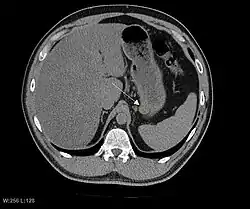

CT image of a GIST in the gastric cardia. The lesion appears submucosal, is hypervascular and protrudes intraluminally. Upper GI bleeding led to endoscopy, finding an ulcerated mass.

Non-enhanced CT image of a small GIST in the posterior stomach wall (arrow). The lesion appears subserosal. Incidental finding.

The purpose of radiologic imaging is to locate the lesion, evaluate for signs of invasion and detect metastasis. Features of GIST vary depending on tumor size and organ of origin. The diameter can range from a few millimeters to more than 30 cm. Larger tumors usually cause symptoms in contrast to those found incidentally which tend to be smaller and have better prognosis.[4][20] Large tumors tend to exhibit malignant behavior but small GISTs may also demonstrate clinically aggressive behavior.[21]

Preferred imaging modalities in the evaluation of GISTs are CT and MRI,[23]: 20–21  and, in selected situations, endoscopic ultrasound. CT advantages include its ability to demonstrate evidence of nearby organ invasion, ascites, and metastases. The ability of an MRI to produce images in multiple planes is helpful in determining the bowel as the organ of origin (which is difficult when the tumor is very large), facilitating diagnosis.